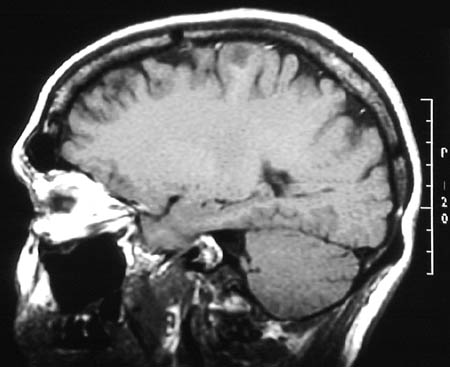

These enhanced MRI scans in sagittal view reveal the presence of a small, ill-defined mass in the superior left frontal lobe. This is an

oligodendroglioma

.